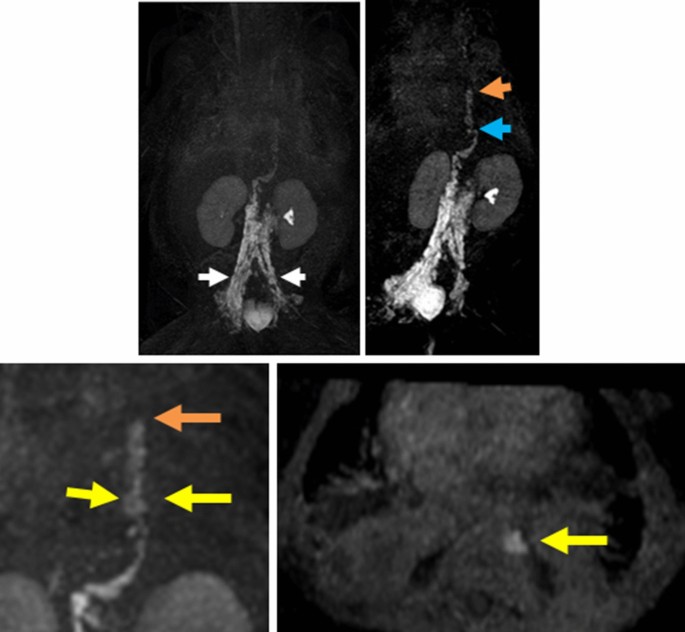

For NIRFLI, described previously [4], performed under FDA (IND 122,035) and institutional IRB approval, intradermal injection of 0.05 cc of 0.25 mg/mL of indocyanine green (ICG; Akorn, Lake Forest, IL) to each dorsal foot was followed by observation for 1 h, and then injection to each hand was followed by observation for 20 min. Images revealed normal fluorescent dye uptake into leg lymphatics and inguinal lymph nodes; however, dye uptake into arm lymphatics was not observed—only diffuse, faint fluorescence (Fig. 1). This abnormal drainage pattern may have shown lymphedema consistent with lymphatic abnormalities commonly seen in Noonan syndrome patients, or that impaired drainage from the left-hand injection was due to high pressure in the central vein secondary to heart failure, considering that thrombotic occlusion of the subclavian veins had been ruled out by prior Doppler studies. Because NIRFLI was unable to identify a site of leakage, Coronal 3D T1 mDixon FFE dynamic MRL utilizing a 3 T Philips Ingenia MR scanner (Philips, Best, Netherlands) was then performed. 1.4 cc Gadavist (Bayer, Whippany, NJ), diluted 1:2 in normal saline, was injected into inguinal lymph nodes using ultrasound guidance. Firstly, MRL confirmed that the thoracic duct was located in the left mediastinum, explaining why the thoracic duct could not be identified during right thoracotomy. Opacification was promptly seen in the right retroperitoneal lymphatics, with chylolymphatic reflux in the left retroperitoneal lymphatics, and hiatus-level thoracic duct dilation. Furthermore, contrast leak from the thoracic duct proximal to the level of the T9 vertebra along the left paravertebral region, where thoracic duct caliber decreased, was observed (Fig. 2).

Selected serial MIP (maximal intensity projection) images of coronal 3D dynamic MR lymphangiogram performed at 1-min intervals for 30 min after inguinal lymph node injection of diluted gadolinium contrast. Progression of lymph flow into ectatic retroperitoneal lymphatics (white arrow), ectatic thoracic duct (blue arrow) with stricture of the thoracic duct (orange arrows) in mid-thoracic region and chyle leak into the pleural space at mid-thoracic level (yellow arrows)